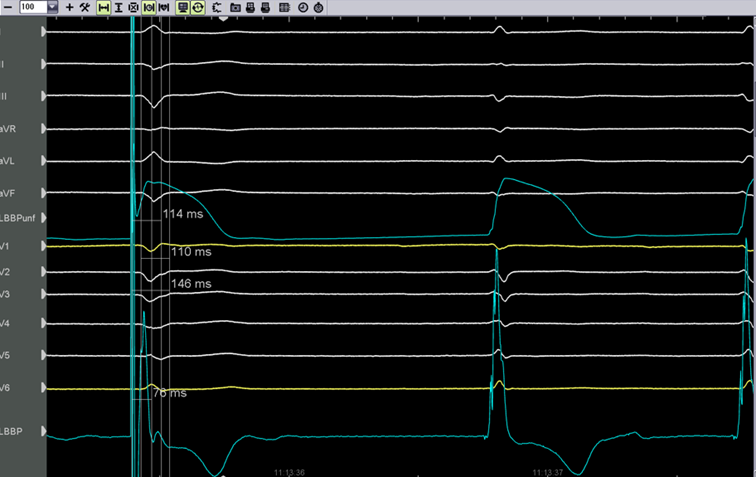

Das Ruhe-EKG (Bild 1) zeigte einen SR, HF 66/min, AV-Block I°, PQ 360ms, QRS 90ms, QTc 400ms, eine Niedervoltage und T-Negativierungen in III, V3 und V4.

Ruhe-EKG

Bild 1: Ruhe EKG

Bild 5: perioperatives 12Kanal-EKG mit LBBP-Signalen gefiltert (LBBP) und ungefiltert (LBBPunf): Links unipolar stimulierter QRS (bei 5V/0,5ms, (R-wave peak time V6 76ms, R-wave peak time V1 114ms, QRS 110ms, QRS von Beginn Stimulus 146ms)) und rechts intrinsischer QRS-Komplex. Pfeil zeigt auf das Faszikelpotential.